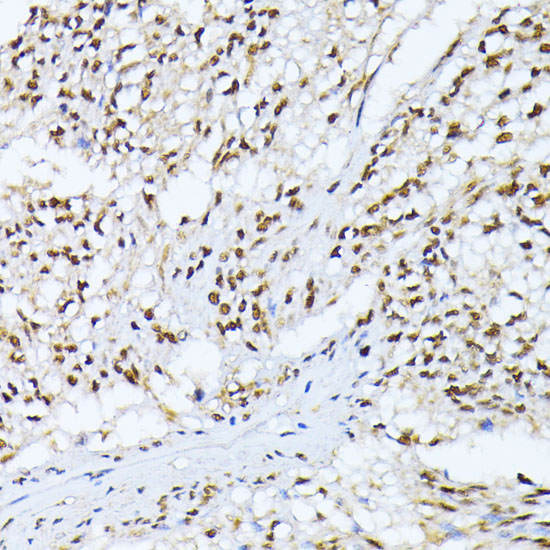

ApplicationWB, IHC, IF; Recommended dilution: WB 1:1000 - 1:4000, IHC 1:50 - 1:200, IF 1:50 - 1:100